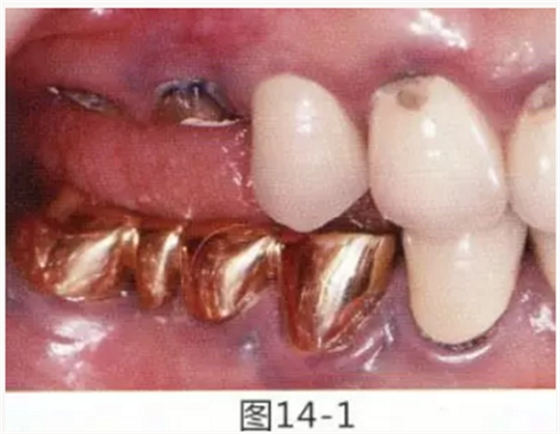

病例5

為了提高對(duì)修復(fù)體的術(shù)后效果,以生物學(xué)寬度,獲取附著齦為目的進(jìn)行游離齦移植的病例

圖14-1 修復(fù)體周圍角化牙齦較少,很難進(jìn)行清潔的狀態(tài),并有緣下齲壞的發(fā)生。

圖14-2,3 徹底去除齲壞后,試圖通過(guò)游離齦移植獲取生物學(xué)寬度和附著齦。

圖14-4~6修復(fù)體周圍角化牙齦較少,很難進(jìn)行清潔的狀態(tài),并有緣下齲壞的發(fā)生。

圖14-7 配戴最終修復(fù)體完成5年后的狀態(tài)。保持良好。